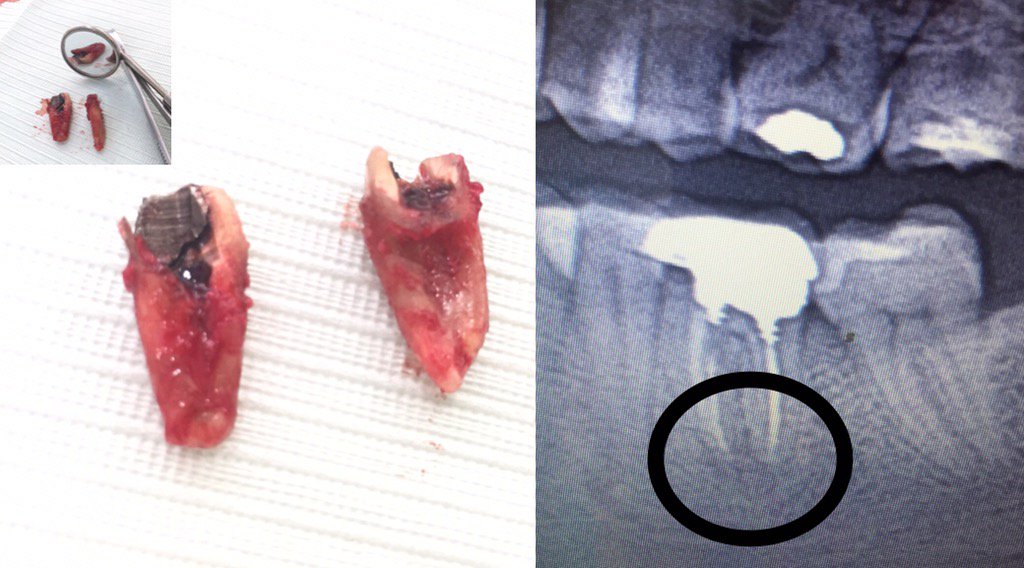

Dr.Hesna Huseyni

@hesnahuseyni

#prosthodontist

#dentist